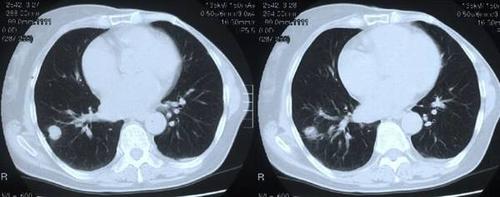

肺癌晚期 胸片

肺癌晚期 胸片,肺癌胸片晚期

肺癌胸片晚期

肺癌ct图片胸片

肺癌胸片

肺癌CT